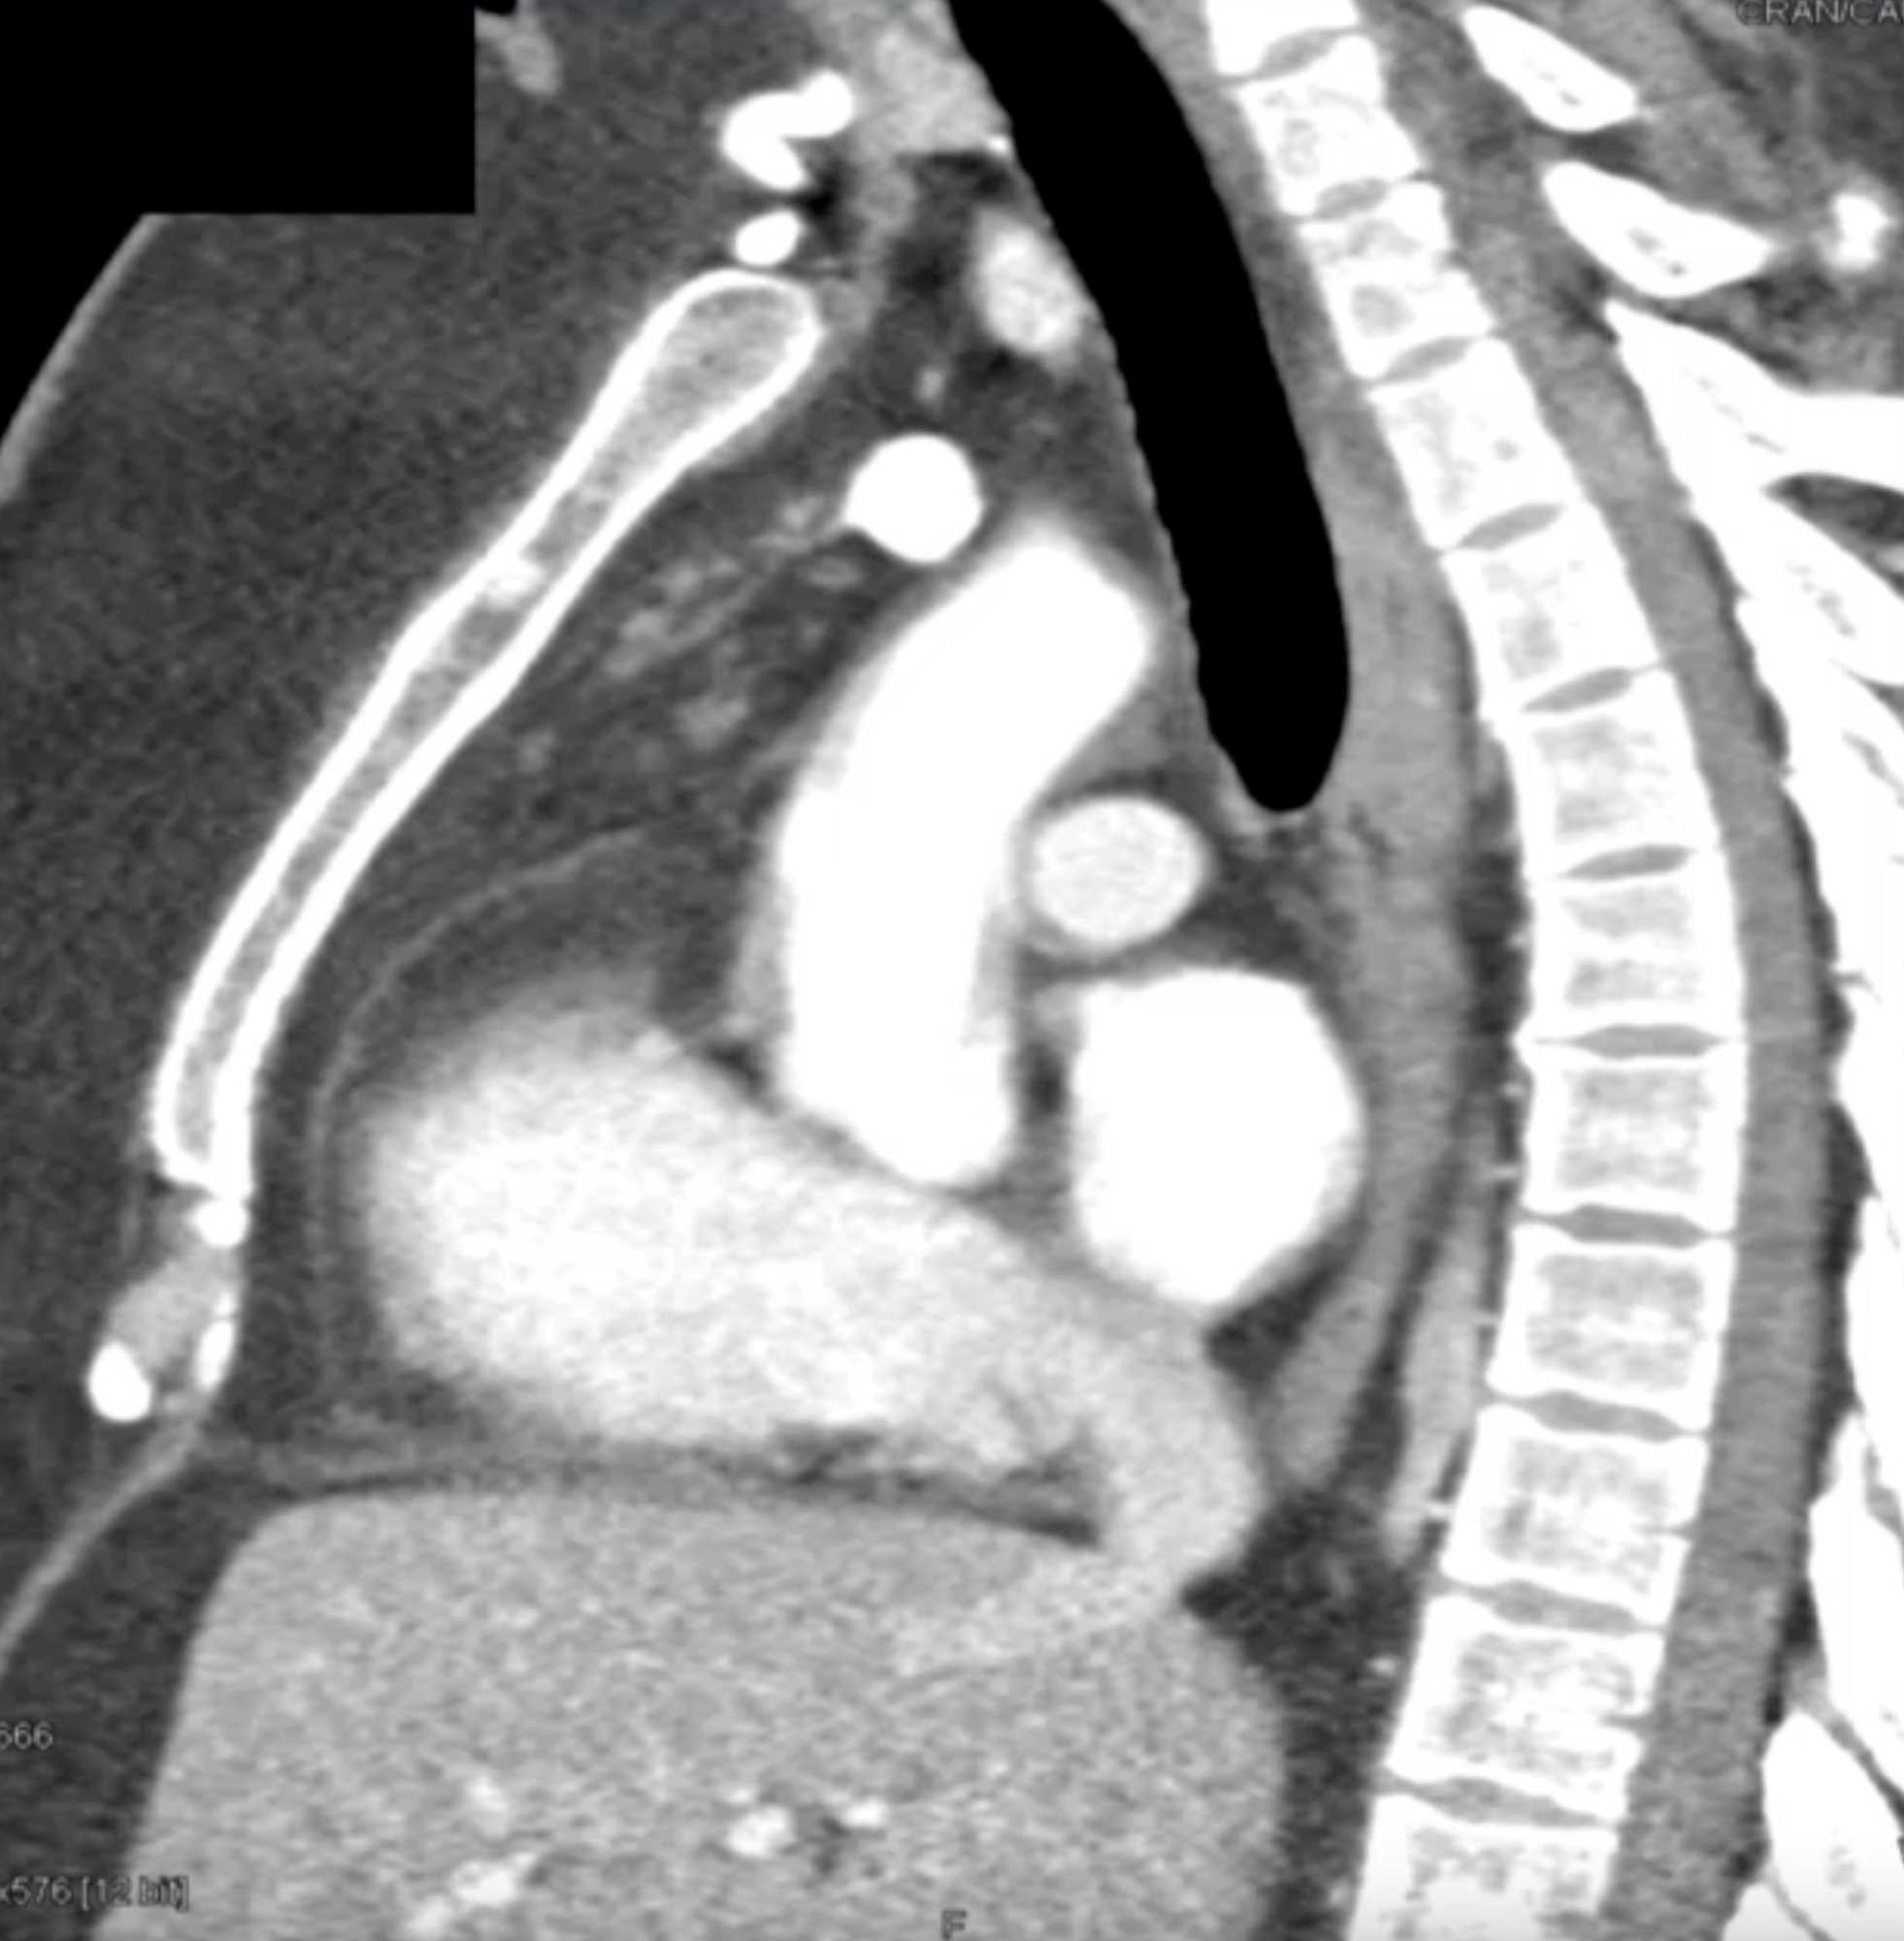

Thymolipoma